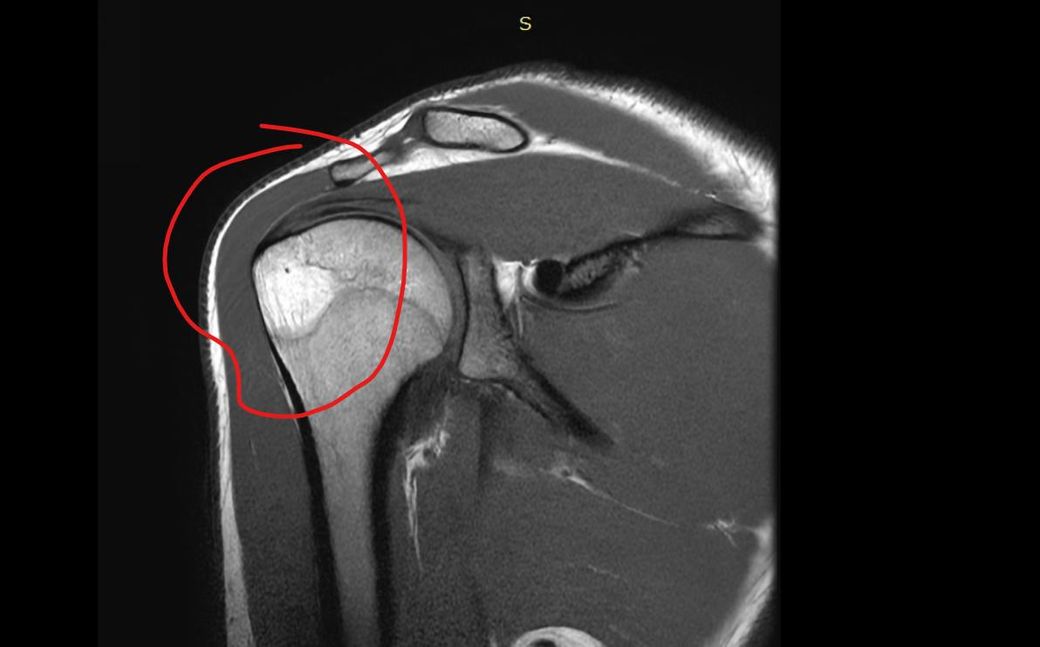

어깨 골수부종인가요 ? 뼈멍인가요 미세골절인가요 사고나고 뼈에 심하게 멍들었다고 했긴했습니다 전 잘모르겠어서 질문 해봅니다

• 4번 째 사진

사진만으로 단정은 어렵지만, 표시된 소견은 보통 “골수부종(=뼈멍)”에 가장 가깝습니다.

치료는 대부분 “안정.사용.제한.소염치료”이며, 정확한 판정은 판독지와 진찰이 필요합니다.

가장 정확한건 mri 촬영한 병원에 문의하셔서 판독지 수령 및 전문의에 판독 소견을 들어보시길 추천드립니다.

또한 미세골절시엔 mri로는 제한 될 수 있기에 초음파 또는 ct 검사를 추가적으로 확인해보시길 바랍니다^^

뼈 내부에 멍처럼 부종이 발생한 골수부종으로 생각되는데요, 자세한 소견은 MRI를 촬영하신 이후 받으신 판독지나 진단서와 같은 서류 혹은 주치의에게 확인을 해보시는 것이 정확하겠습니다.